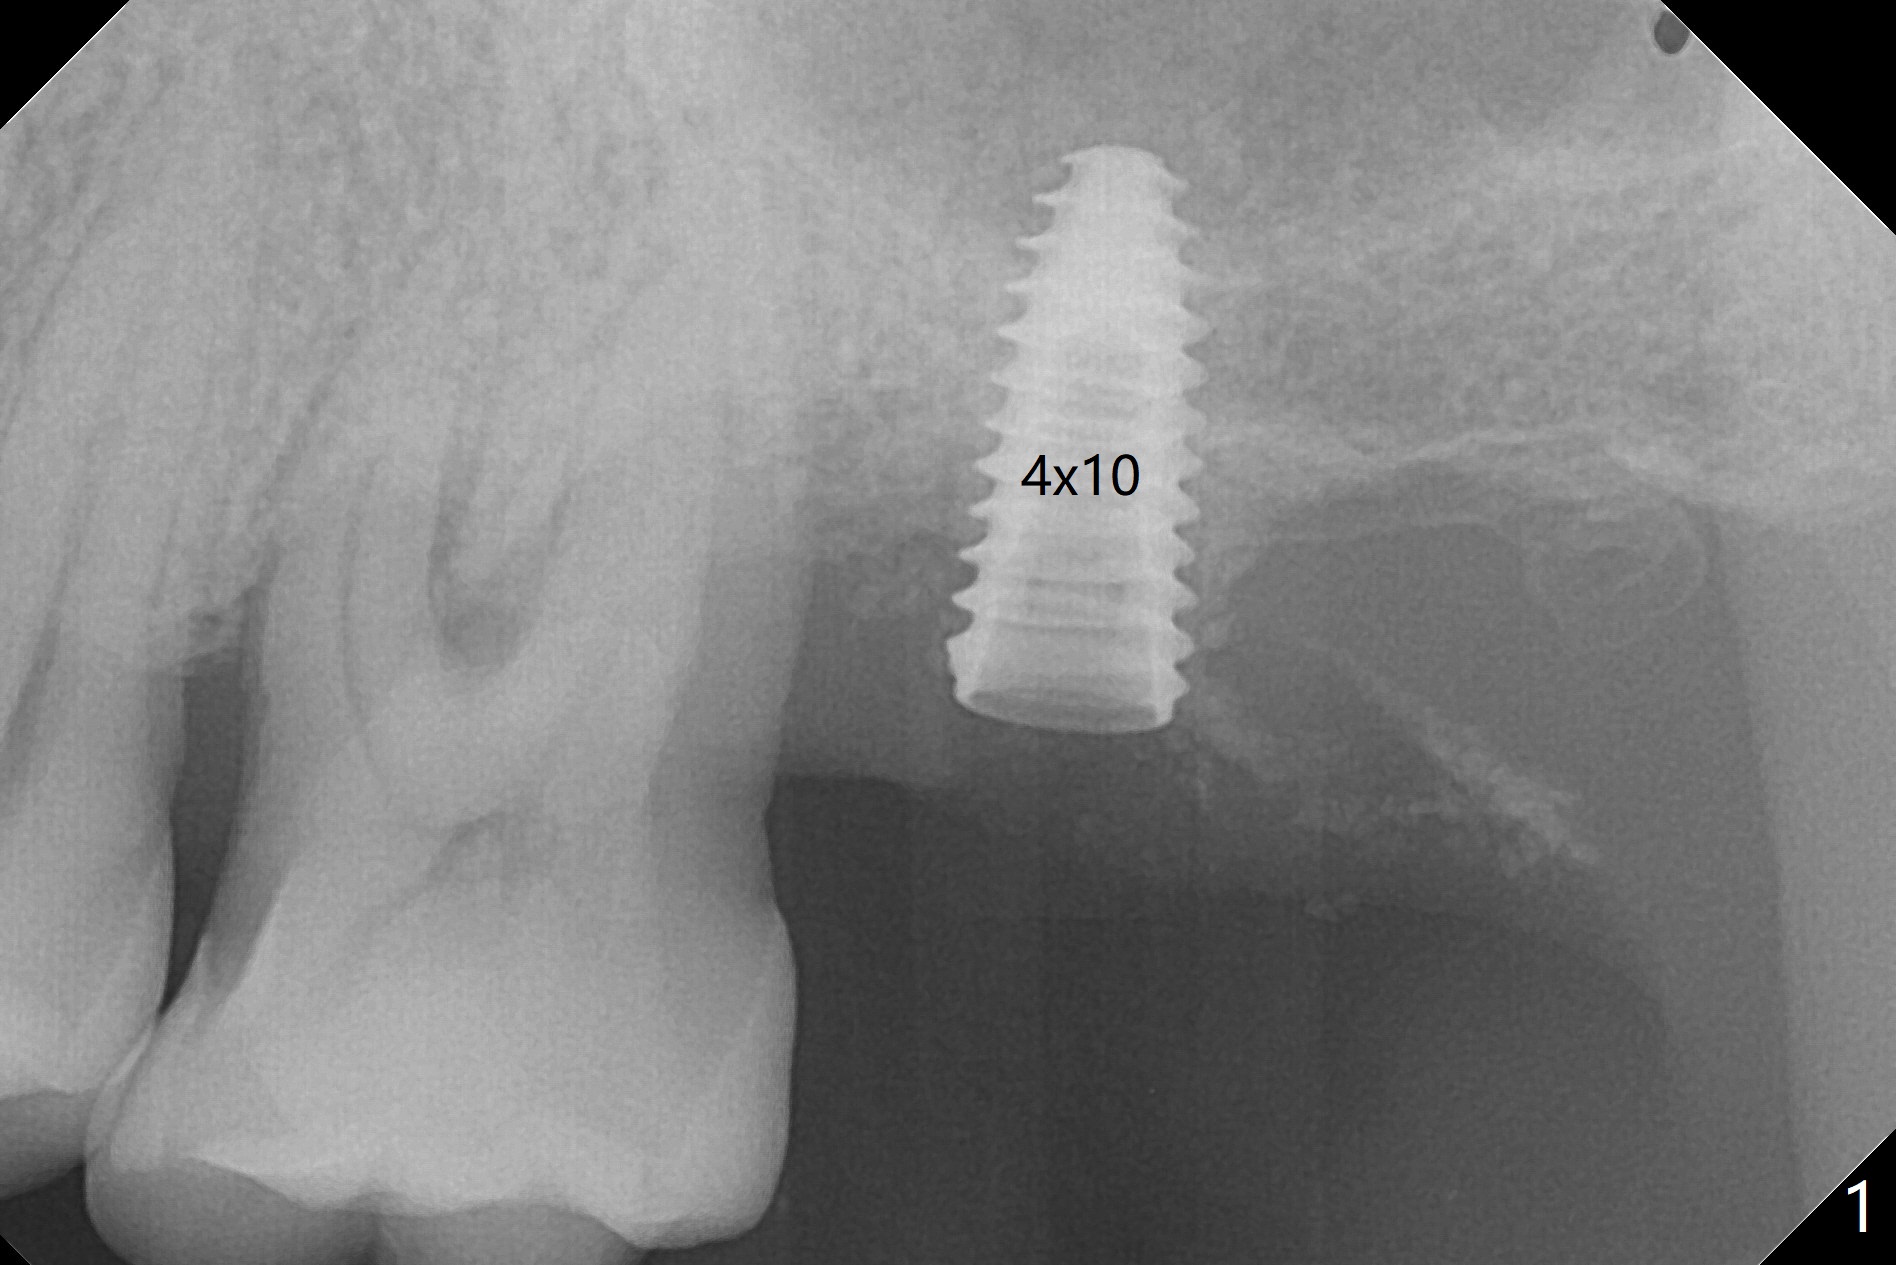

NovaBone Putty修复上颌窦膜

左上7完成初步钻洞,园钻头无法插入导板金属圈,用2.2毫米钻头钻深2毫米,窦膜似乎完整,在没有骨粉情况下,使用4x10毫米报废植体做上颌窦提升(图一),可能一下提升太多,窦膜破了,塞入两小块胶原膜,注入NovaBone

Putty (in

cartridge),植入短小植体(4.5x7毫米,原定(5x8.5毫米)图二),由于稳定性好,使用5.5毫米profile钻头后,放置5.5x4毫米愈合基台(图三)。术后病人没有什么上颌窦不适和分泌物。估计Novo

Bone在上颌窦里凝固了。其实左侧上颌窦粘膜术前增厚(图四,五:L),人工骨仿佛弥撒在上颌窦膜中(图六)。术后一周病人没有任何鼻窦症状。术后4.5月旋转愈合基台时,病人感到疼痛,终止取模(图七),两个月后复诊,做progressive loading。术后5.5月旋转愈合基台时,植体一起出来,但是上颌窦膜没有破,放置大一号植体(报废)扭力不够(图八),再大一号扭力可以(图九),放置愈合帽。由于邻牙长(图九:双箭头),牙周敷料逗留三周不掉(图十:P)。撤除后,伤口愈合正常。The